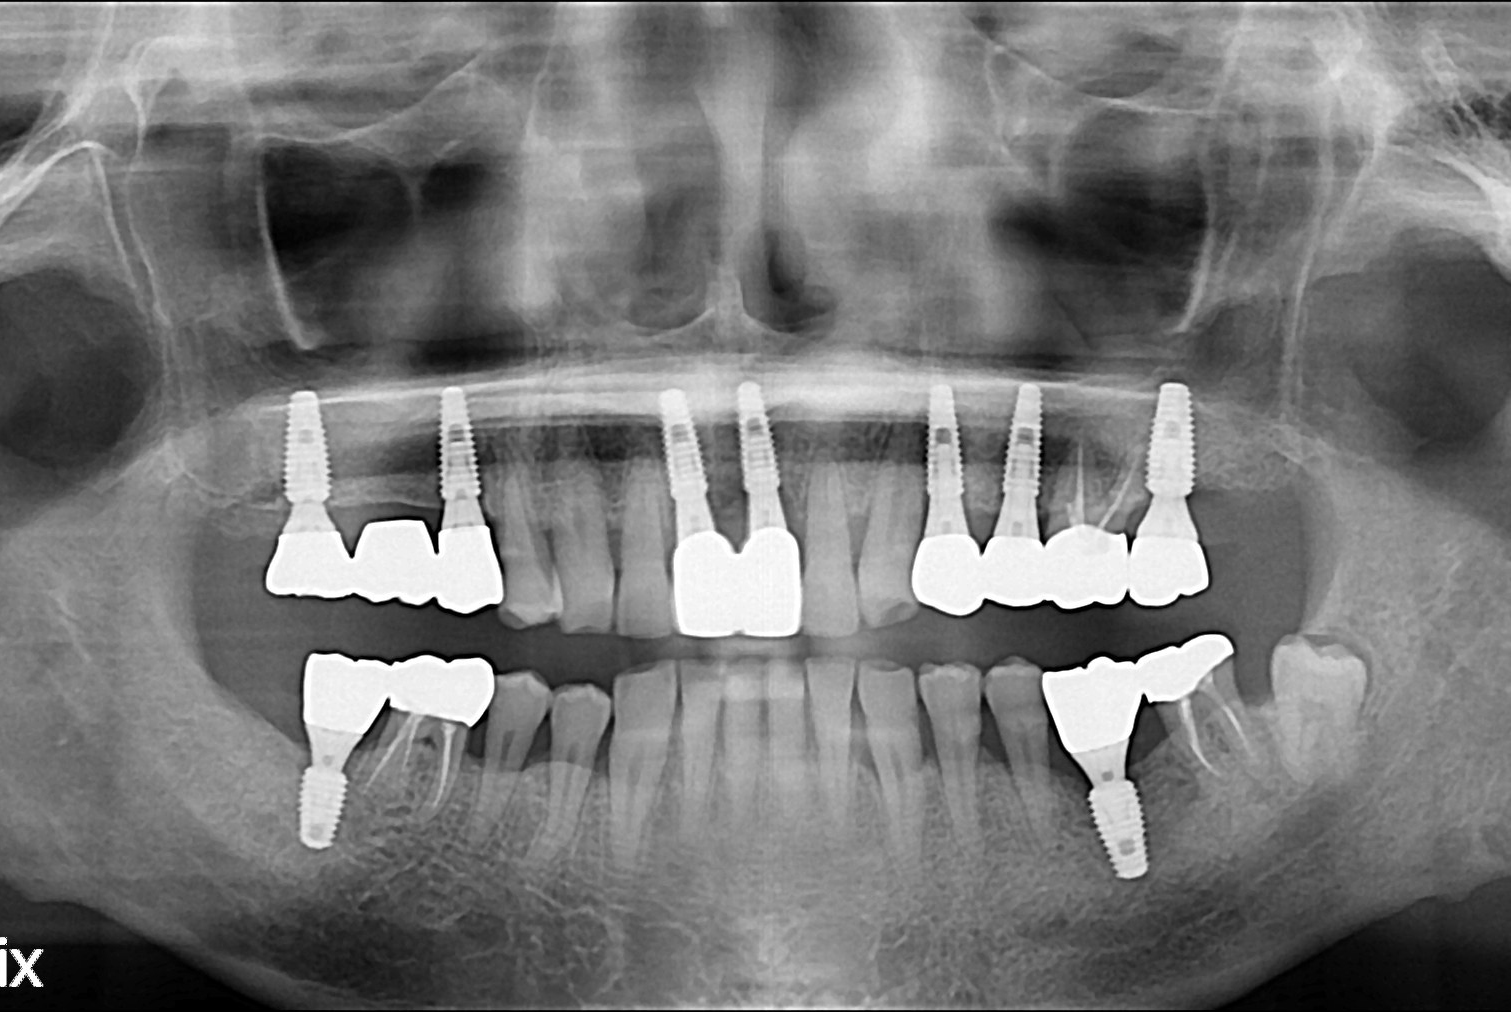

치료전 : 2018-10-26

후.jpg

치료후 : 2018-11-27

세종치과는 많은 환자와 다양한 케이스를 바탕으로 항상 편안한 임플란트 수술을 제공하고자 노력하고,

오래동안 튼튼히 쓸 수 있는 임플란트 수술을 가장 큰 목표로 삼고 있습니다